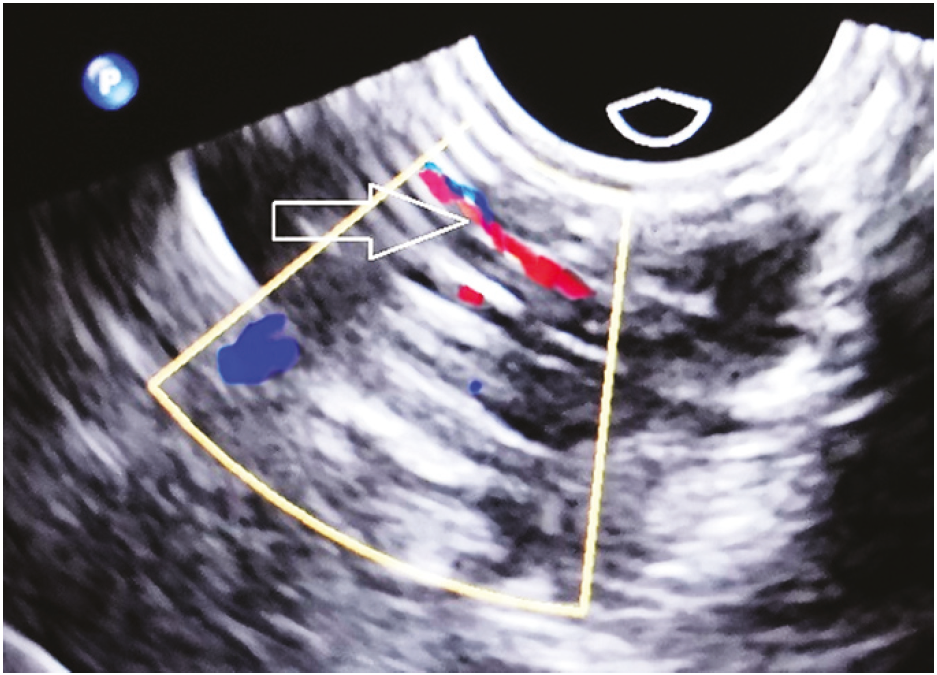

Для исключения наличия паратонзиллярного абсцесса дополнительно к проведенным инструментальным исследованиям выполнено УЗИ паратонзиллярной клетчатки. При трансоральном ультразвуковом исследовании глотки в В-режиме и с цветным допплеровским анализом в правой паратонзиллярной области структура однородная, анэхогенные и гипоэхогенные очаги не определяются. Данных за абсцесс при ультразвуковом исследовании не выявлено. Визуализируются внутренняя сонная артерия и наружная сонная артерия. Выявлено аномальное расположение сосудов: ветви наружной сонной артерии находятся на глубине до 10 мм (рисунок 1).

Рисунок 1. Визуализация ветви наружной сонной артерии на сонографическом изображении правой паратонзиллярной области.

Проведение трансорального ультразвукового исследования глотки позволило исключить признаки формирующегося абсцесса в паратонзиллярной области [13, 14]. В представленном клиническом наблюдении ветви наружной сонной артерии в паратонзиллярной клетчатке располагались на глубине до 10 мм, исследование проводилось в области наибольшего выбухания.